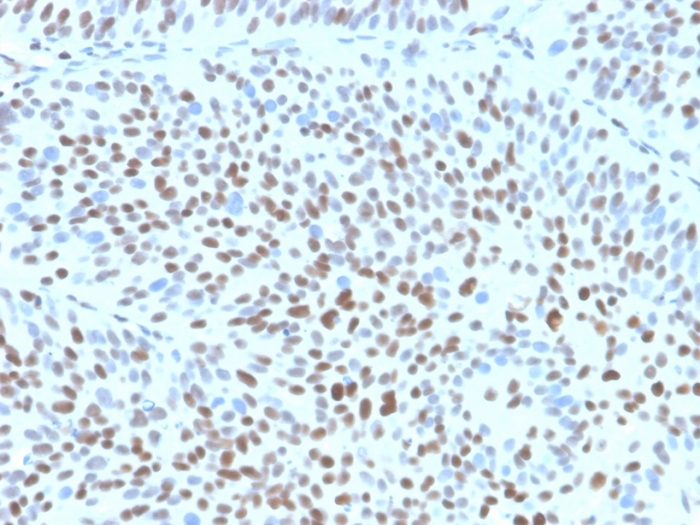

IHC analysis of formalin-fixed, paraffin-embedded human bladder. Strong nuclear staining using KIP1/1355R at 2ug/ml in PBS for 30min RT. HIER: Tris/EDTA, pH9.0, 45min. 2°C: HRP-polymer, 30min. DAB, 5min.